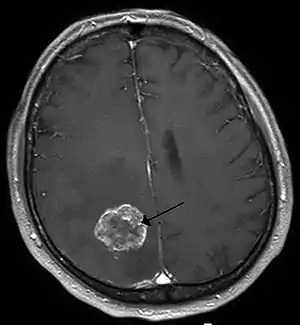

![]() Пухлина головного мозку на знімку МРТ Пухлина головного мозку на знімку МРТ | |

Основний метод діагностики: магнітно-резонансна томографія (МРТ).